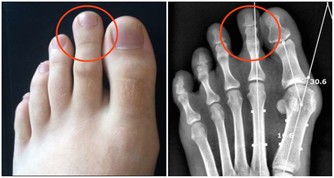

4、癒合能力差

身體淤青後很難消下去;或者傷口相比其他人來說,癒合得很慢,很可能過了一段時間後還沒有完全癒合,而且還容易受到感染,出現紅腫、流膿的情況。